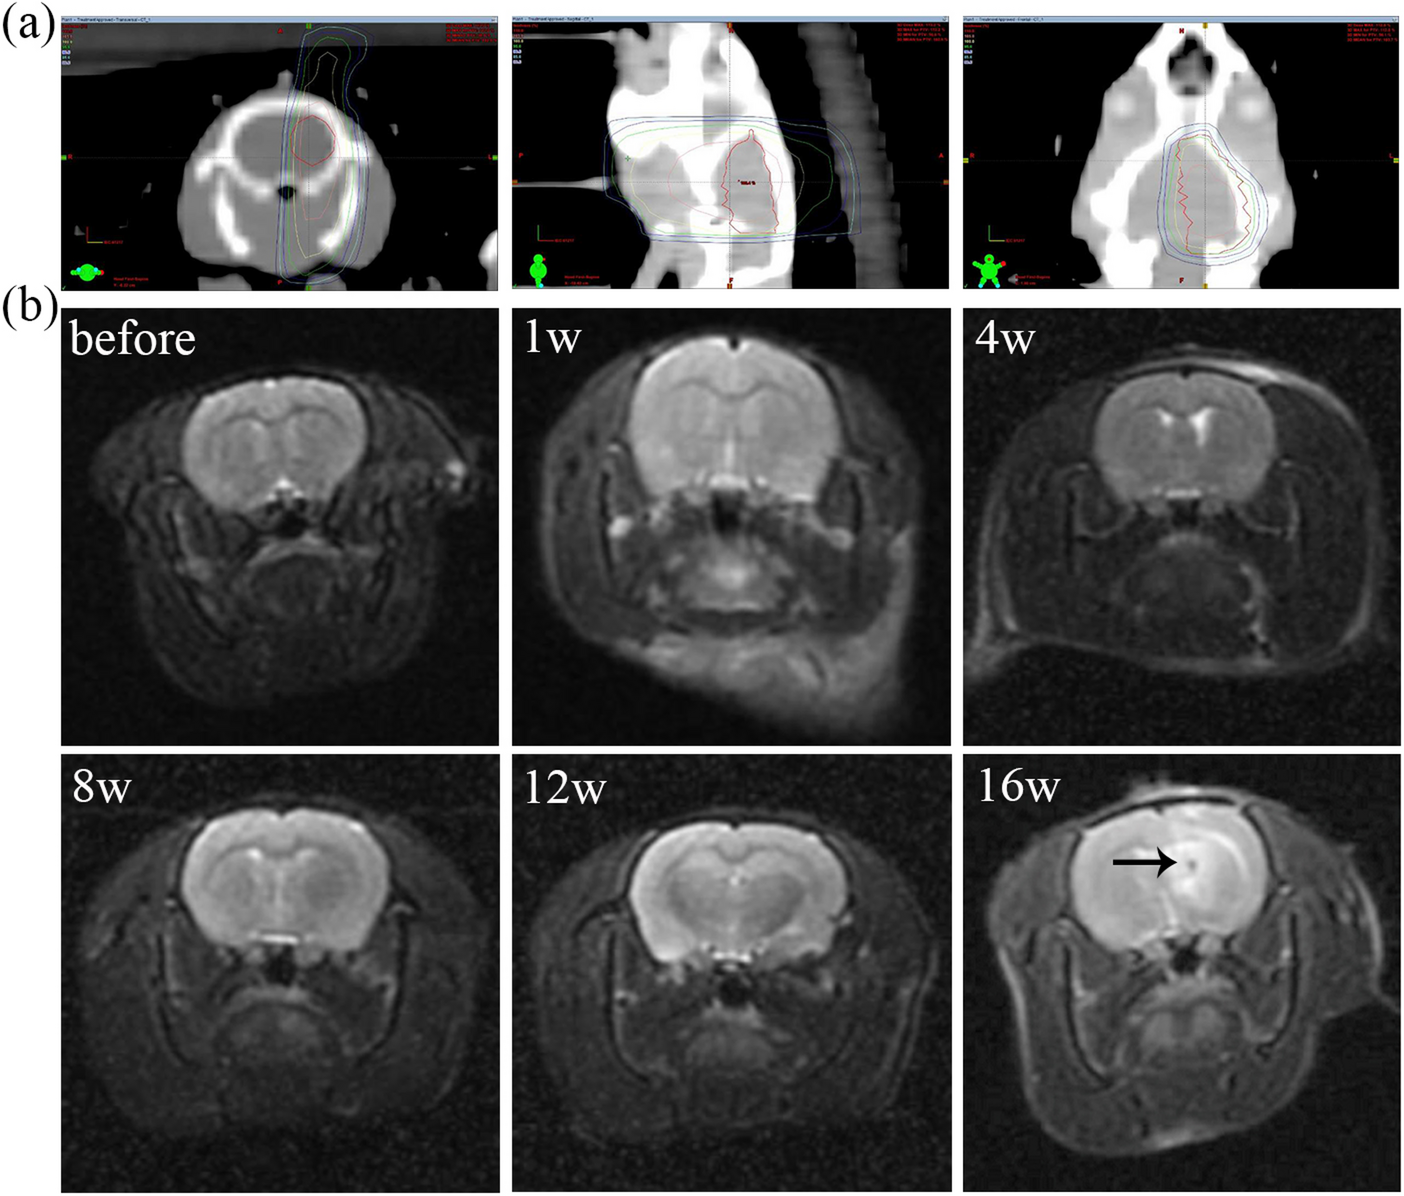

Fig. 3

Establishment of SD rat radiation brain necrosis model. (a) Radiotherapy dose planning. (b) MRI scan image of radiation brain necrosis model before irradiation and at 1/4/8/12/16th week of irradiation. The arrow represents the lesion of radiation necrosis.